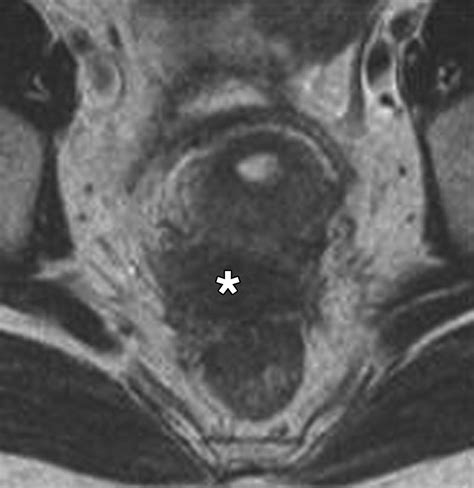

Diagnosing conditions affecting the Posterior Cul De Sac often involves a combination of medical history, physical examination, and diagnostic tests. Some of the most common diagnostic techniques include:

• MRI: An MRI uses magnetic fields and radio waves to create detailed images of the body's internal structures. This test can provide valuable information about the Posterior Cul De Sac and surrounding tissues.